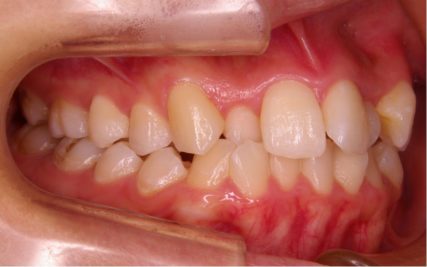

でこぼこ/20代女性

- 不正咬合/叢生(でこぼこ)

- 上下とも前歯のスペース不足が認められた。歯のサイズと顎の幅とのバランスが不調和な事が原因の1つとして考えられる。

- 上顎両側4番・上顎両側8番・下顎両側4番・下顎両側8番抜歯

- マルチブラケット装置(セルフライゲーションブラケット)/歯科矯正用アンカースクリュー

- 前歯部のでこぼこが解消され、正常咬合を獲得する事が出来た。又、歯科矯正用アンカースクリューを用いる事で抜歯スペースを有効に利用できた。